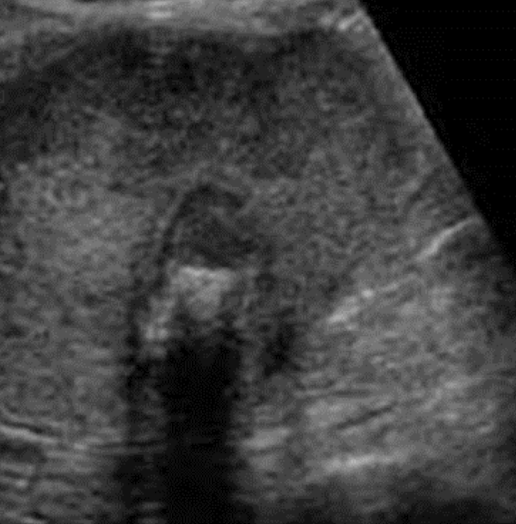

gangrenous cholecystitis

necrotic GB due to prolonged infection

s/s: painful

SONO: thickened irregular edematous wall; pericholecystic abscess; perforations; echogenic densities that fill the lumen of the GB that has:

no shadow

not gravity dependent

no layering effect due to increased viscosity of the bile

??